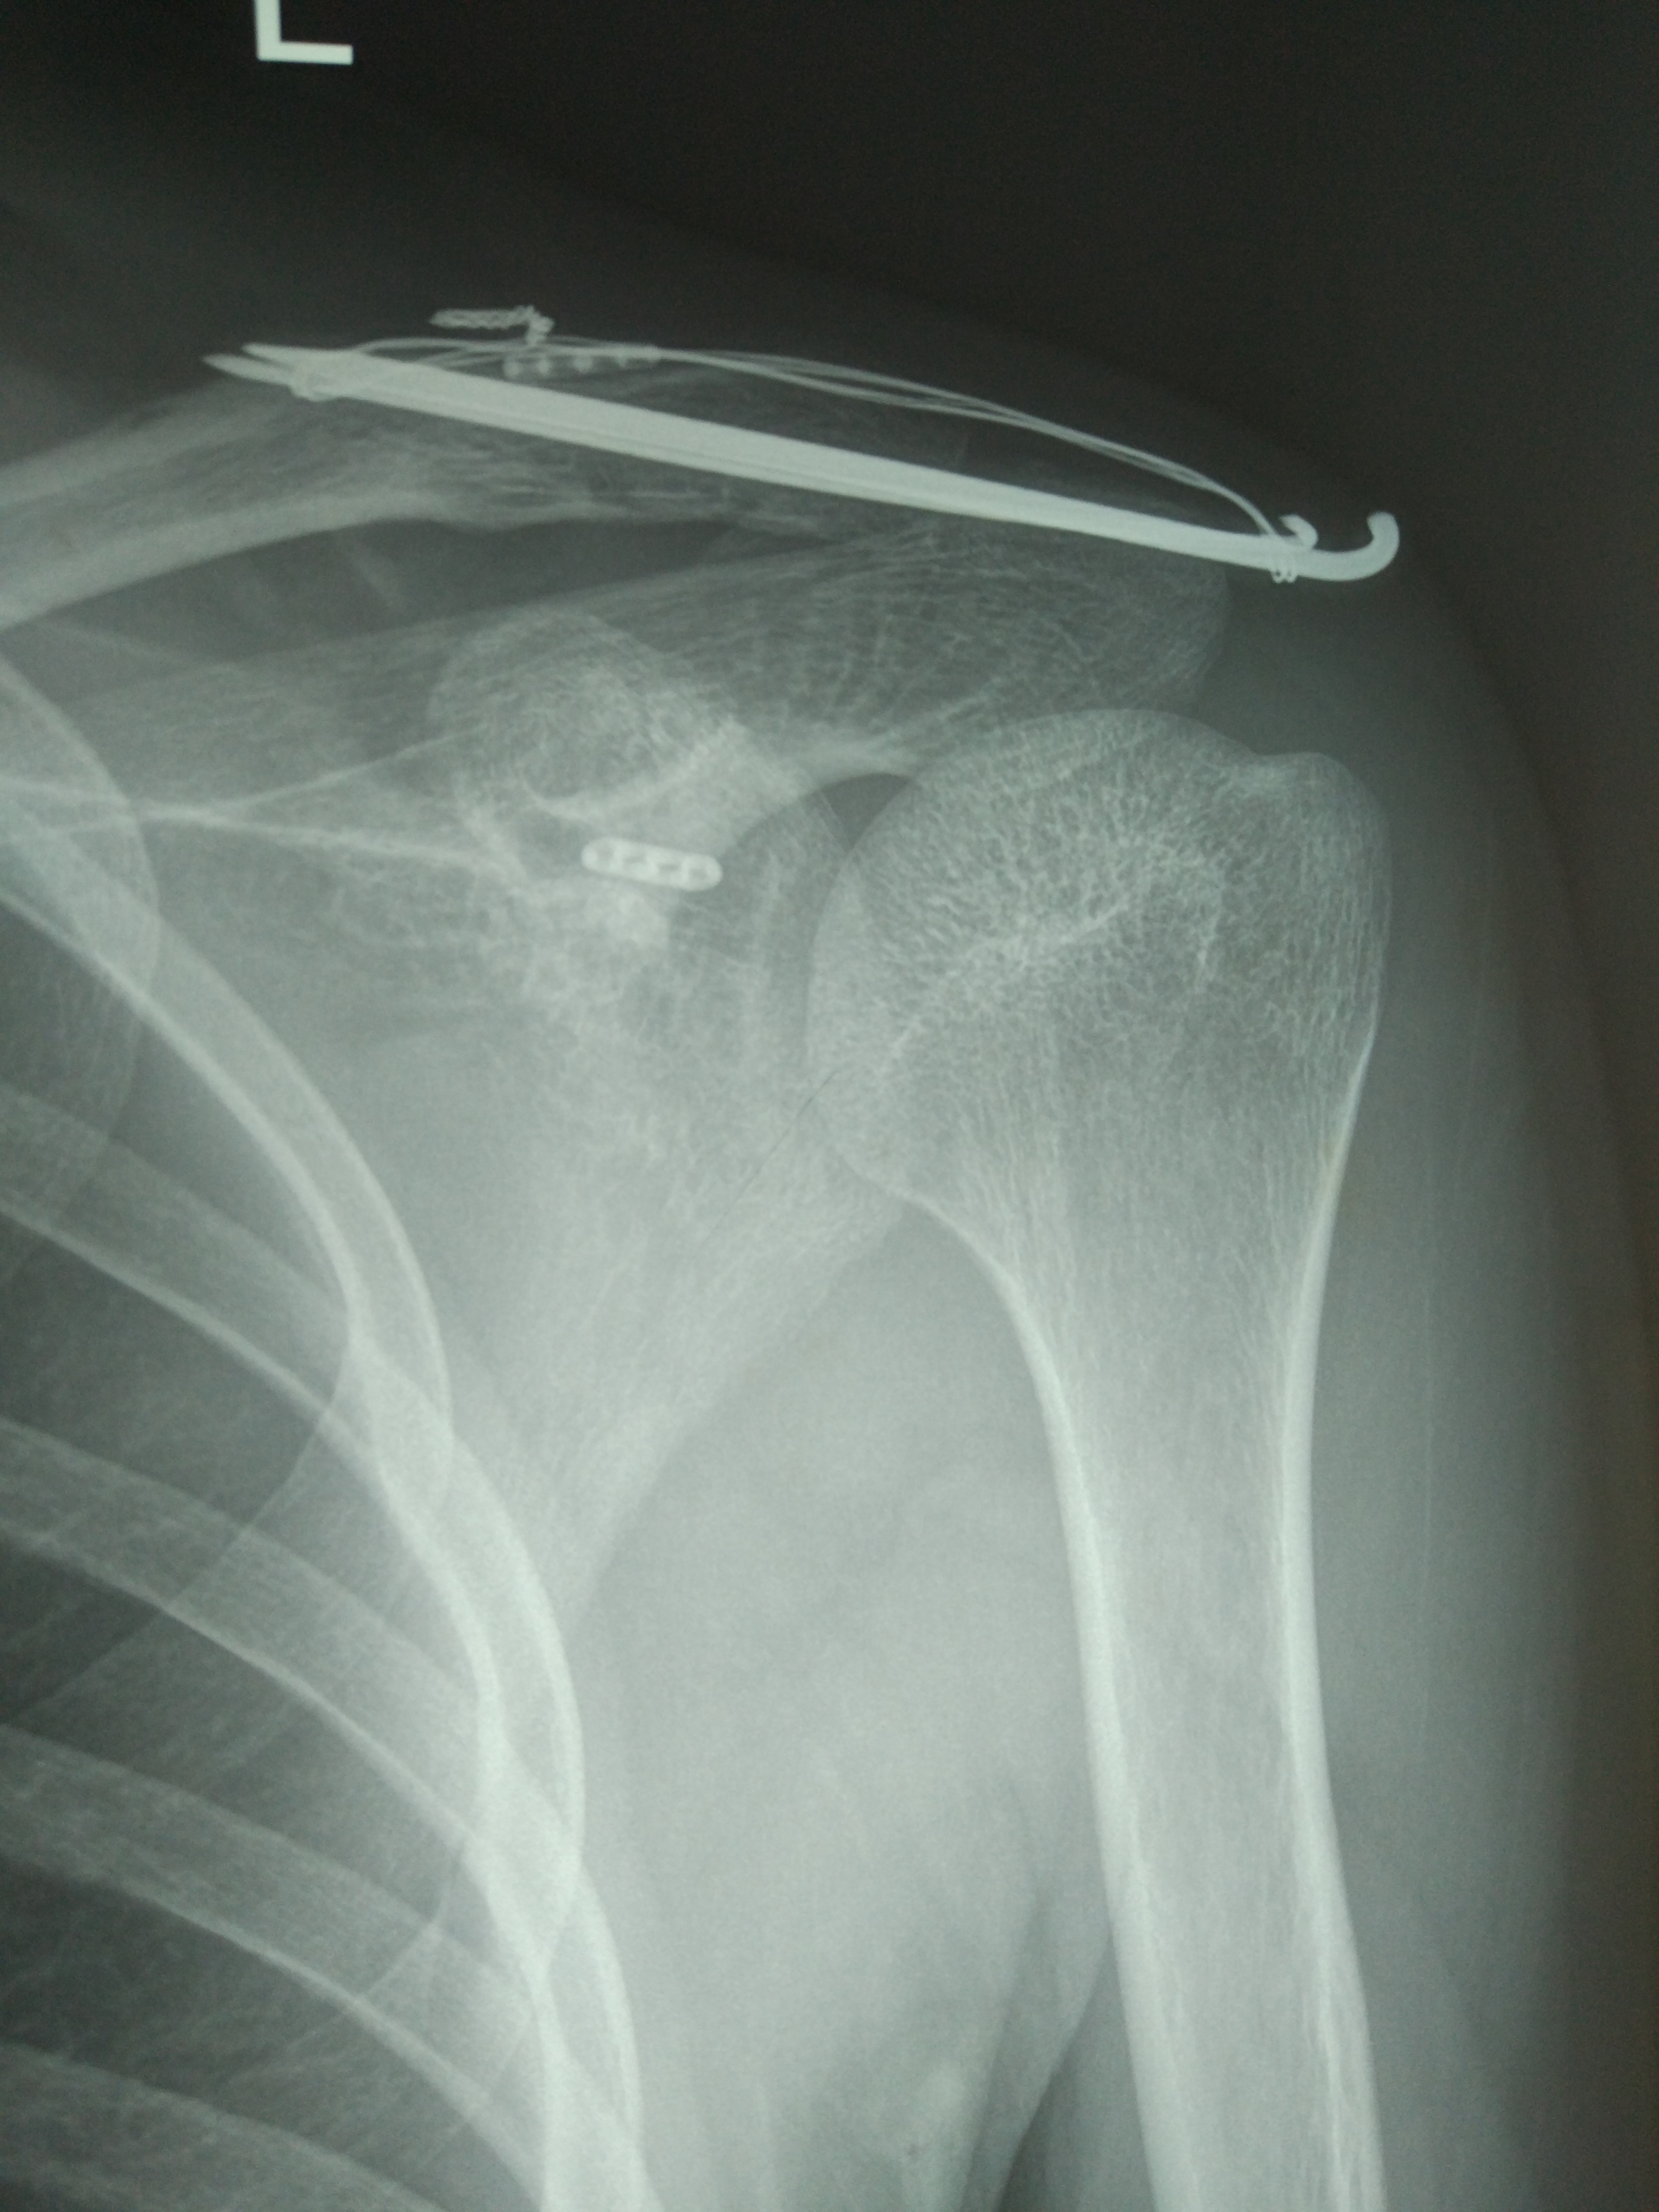

锁骨骨折吧

老哥们,术后三个月,长好了没?医生说术后六个月拆除,这三个月总感觉浑身难受。

我的是钢板加螺钉内固定,你这和我不一样!

我这个很少见吗?[黑线][黑线][黑线]

克氏针

自己骨折也有点会看片子了,好像恢复不错,骨折在哪里看不清

看不出骨折在哪里岂不是[滑稽]………还是听医生的话吧,再难受三个月估计会好

这个可以拆了,已经六个月了,很开心

拆了一个多月了,身体还是没以前舒服[泪]

拆了三个多月了,还是没以前舒服[泪]

拆了10个月,还是没以前舒服